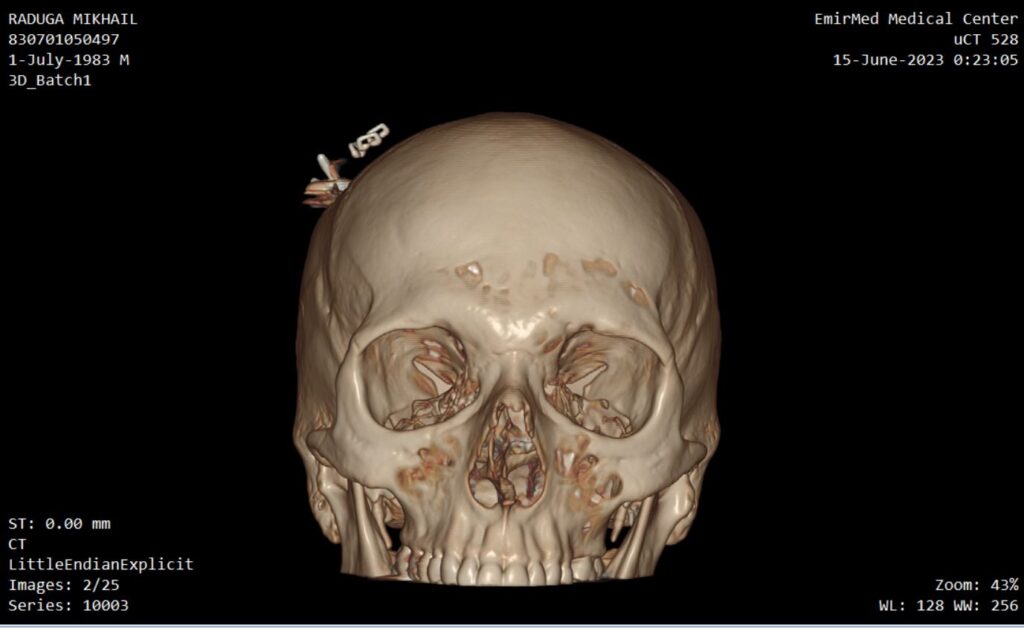

Implant

Device for electrical stimulation

Photos of computed tomography